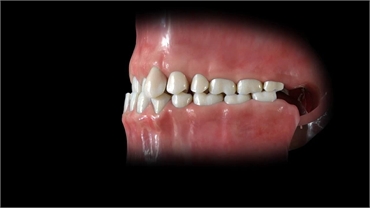

A proper bite needs to be established in a growing child. A child falling in the age group of 7-10 years should be closely monitored every 6 months by a dentist. During this stage the upper and lower front teeth (permanent central incisors) and the upper and lower back teeth (first permanent molars) find their way inside the oral cavity. When one or both upper central incisors erupt in an abnormal pattern, it often results in an abnormal closure of the anterior (front) teeth bite. This results in one or both of the upper front teeth being placed behind the lower incisors. Thus, the upper tooth or teeth get locked inside the lower front teeth and the patient is said to exhibit an anterior crossbite.